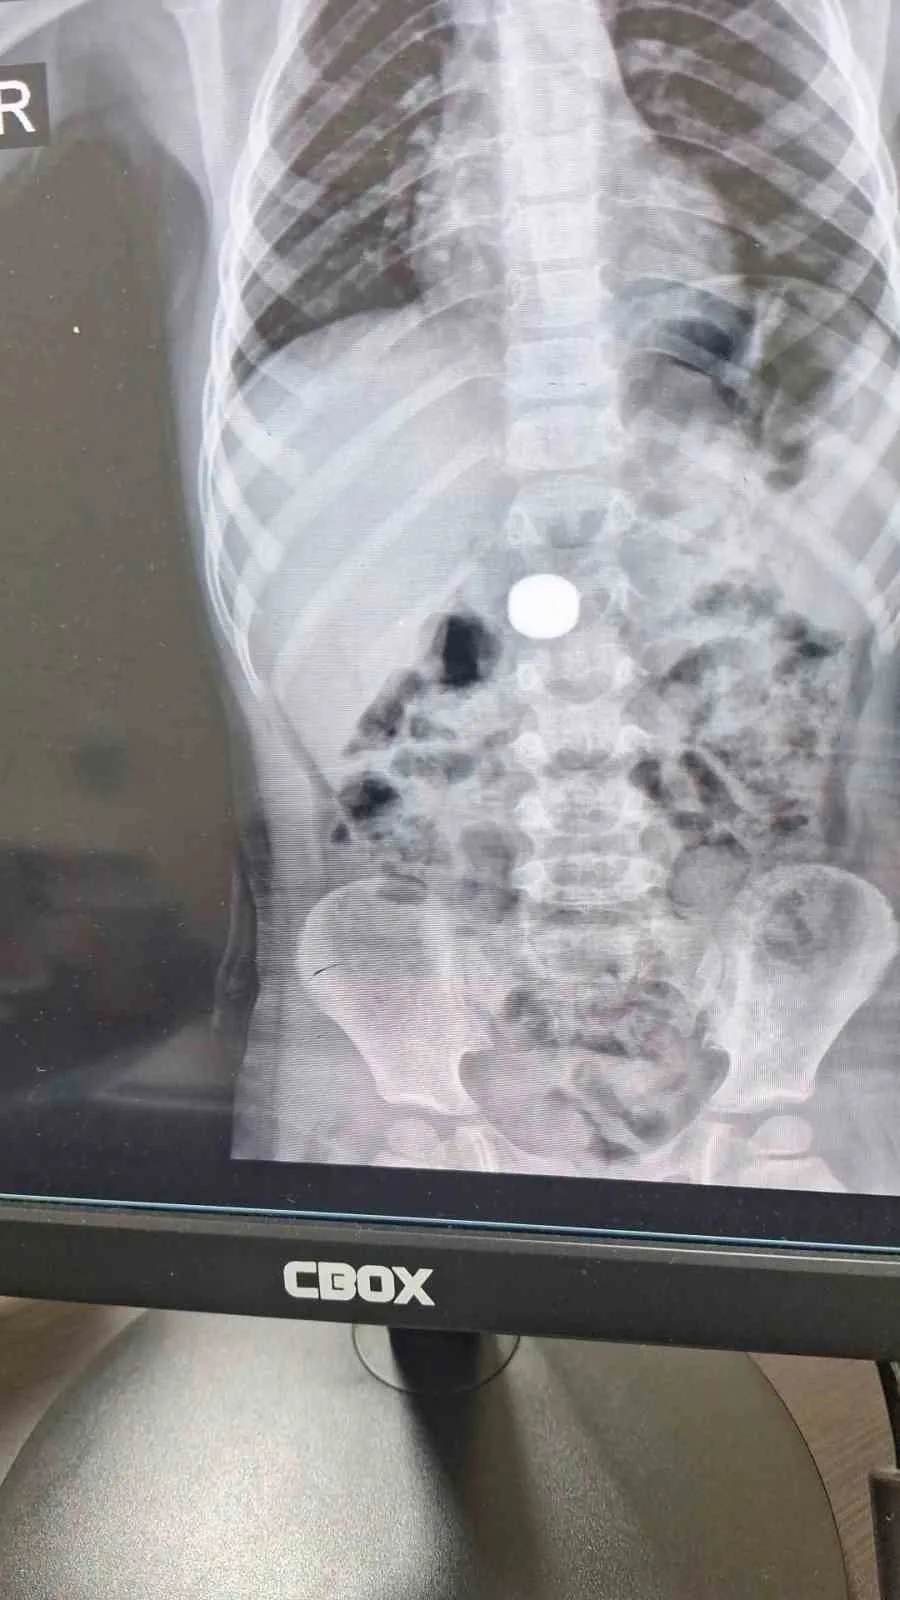

Karaman’da 4 yaşındaki İ.K.’nin mıknatıs yuttuğundan şüphelenen ailesi, Karaman Eğitim ve Araştırma Hastanesi Acil Servisi’ne başvurdu. Yapılan tetkiklerde çocuğun ince bağırsağında iki adet mıknatıs bulunduğu tespit edildi.

Gözlem altına alınan çocuğun sağlık durumu 5 gün boyunca takip edildi. Çocuk Cerrahisi Uzmanı Doç. Dr. Mehmet Uysal, takip süresince çekilen filmlerde mıknatısların yer değiştirmediğini belirtti.

Doç. Dr. Mehmet Uysal, hastanın genel anestezi altında ameliyata alındığını ifade ederek, “İnce bağırsakta iki mıknatısın birbirine yapışık halde olduğunu gördük. Gerçekleştirdiğimiz operasyonla mıknatısları çıkardık. Ameliyat sonrası hastamız üçüncü gününde taburcu edildi. Şu an genel durumu iyi” dedi.